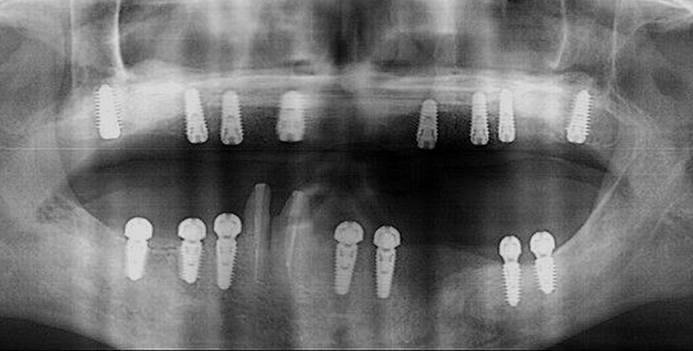

Clinical case: Full-mouth implants for mandibular & maxilla - restored using mixed prostheses

- Courtesy of Dr. Hyun Jun Kim, Korea -

Keywords

AnyRidge, full-mouth implants, mandibular, maxilla, edentulous, full mouth rehabilitation, Octa abutment, long-term clinical case, biological stability, Dr. Hyung Jun Kim

Products:

AnyRidge implant system